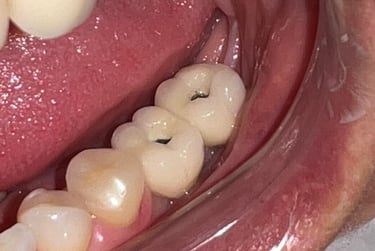

Aspecto clínico final - Imagens originais — nenhuma contém retoques